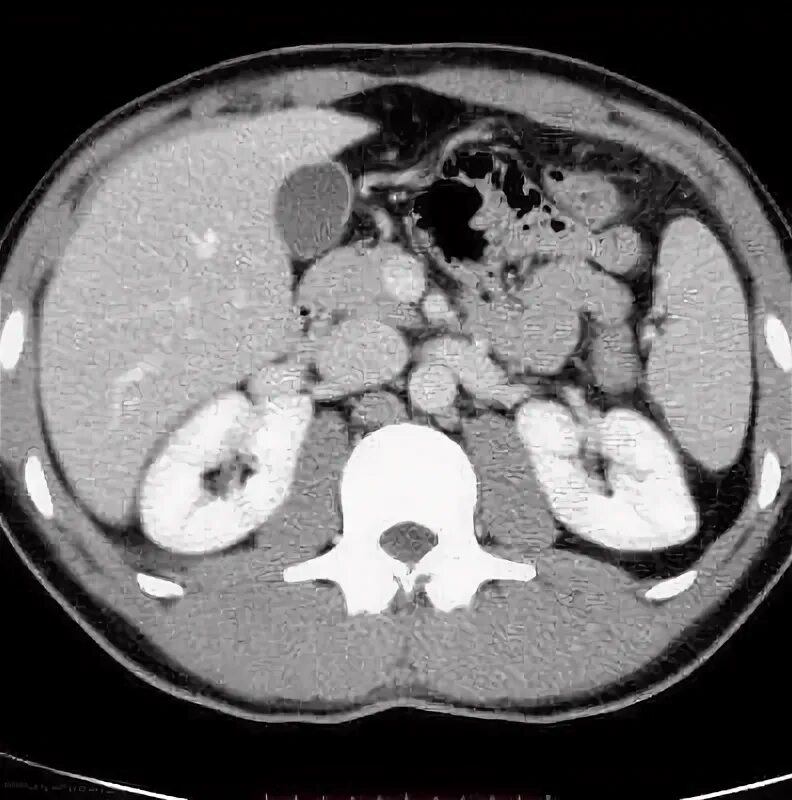

Кт брюшной полости с контрастом как делают